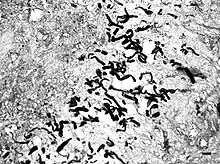

Phycomycosis is an uncommon condition of the gastrointestinal tract and skin most commonly found in dogs and horses. The condition is caused by a variety of molds and fungi, and individual forms include pythiosis, zygomycosis, and lagenidiosis. Pythiosis is the most common type and is caused by Pythium, a type of water mould. Zygomycosis can also be caused by two types of zygomycetes, Entomophthorales (such as Basidiobolus and Conidiobolus) and Mucorales (such as Mucor, Mortierella, Absidia, Rhizopus, Rhizomucor, and Saksenaea).[1] The latter type of zygomycosis is also referred to as mucormycosis. Lagenidiosis is caused by a Lagenidium species, which like Pythium is a water mould. Since both pythiosis and lagenidiosis are caused by organisms from the class Oomycetes, they are sometimes collectively referred to as oomycosis.